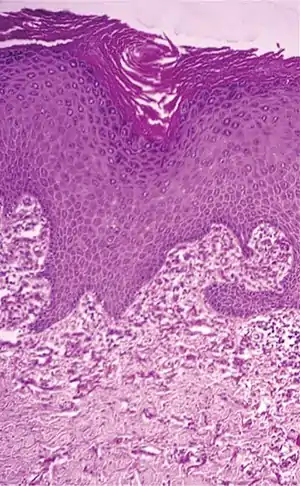

| Histopathology of perforating calcific elastosis: Clumping of short elastic fibers in the dermis.[2] | |

a,b)Perforating calcific elastosis- short elastic fibers in the dermis